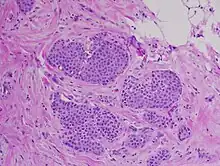

Classically, LN, including LCIS, is characterized by enlargement and distension of acini making up the TDLU by proliferation of monomorphic, dyshesive, small, round, or polygonal cells with loss of polarity and inconspicuous cytoplasm. Essentially, groups of round, almost identical looking cells that fill and expand the lobule spaces, occasionally extending into the adjacent terminal ducts – termed Pagetoid extension.[11] Like the cells of atypical lobular hyperplasia and invasive lobular carcinoma, the abnormal cells of LCIS consist of small cells with oval or round nuclei and small nucleoli detached from each other.[12] Mucin-containing signet-ring cells are commonly seen. LCIS generally leaves the underlying architecture intact and recognisable as lobules. Estrogen and progesterone receptors are present and HER2/neu overexpression is absent in most cases of LCIS.[3] Cell borders are indistinct and neither mitotic activity or necrosis are seen. In addition, in situ and invasive lesions exhibit loss of cellular adhesion, considered a characteristic histologic feature, due to the fact that e-cadherin expression is lost (transmembrane protein involved in epithelial cell adhesion).[2] ALH and LCIS are cytologically indistinguishable, so a quantitative threshold is used to classify lesions into either category. A diagnosis of LCIS requires more than half of the acini in an involved lobular unit to be filled with LN cells and the central lumen of the acini should not be visible.[13] Proliferation of LN cells that do not meet these histological characteristics are either Atypical Lobular Hyperplasia or simply lobular distension. Small degrees of cytologic variation can be observed and subsequent subtypes have been described. However, these subtypes have not been shown to be of clinical usefulness and does not have bearing on whether or not LCIS will progress to full invasive carcinoma.[14]

Lobular Carcinoma In Situ may mimic low grade Ductal Carcinoma In Situ histologically. In these scenarios, pathologists may employ immunohistochemical testing to differentiate between entities.[3] This involves using marked antibodies synthetically developed to bind to target proteins expressed on or inside cells. Specifically, in LCIS, antibodies targeting the e-cadherin protein (or lack thereof) and p120 catenin proteins are used to differentiate LCIS from DCIS. Due to the fact that LCIS shows lack of e-cadherin expression on cell membranes and subsequent p120 catenin buildup in the cytoplasm, lesions that show positive membrane immunoreactivity for e-cadherin are diagnosed as DCIS.[3]